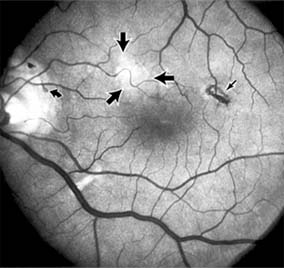

Chapter 10: Retina DISEASES OF THE MACULA AGE-RELATED MACULAR DEGENERATION Age-related macular degeneration is the leading cause of permanent blindness in the elderly. The exact cause is unknown, but the incidence increases with each decade over age 50. Other associations besides age include race (usually Caucasian), sex (slight female predominance), family history, and a history of cigarette smoking. The disease includes a broad spectrum of clinical and pathologic findings that can be classified into two groups: nonexudative ("dry") and exudative ("wet"). Although both types are progressive and usually bilateral, they differ in their manifestations, prognosis, and management. The more severe exudative form accounts for approximately 90% of all cases of legal blindness due to age-related macular degeneration. 1. NONEXUDATIVE MACULAR DEGENERATION Nonexudative age-related macular degeneration is characterized by variable degrees of atrophy and degeneration of the outer retina, retinal pigment epithelium, Bruch's membrane and choriocapillaris. Of the ophthalmoscopically visible changes in the retinal pigment epithelium and Bruch's membrane, drusen are the most typical (Figure 10-1). Drusen are discrete, round, yellow-white deposits of variable size beneath the pigment epithelium and are scattered throughout the macula and posterior pole. With time, they may enlarge, coalesce, calcify, and increase in number. Histopathologically, most drusen consist of focal collections of eosinophilic material lying between the pigment epithelium and Bruch's membrane; they therefore represent focal detachment of the pigment epithelium. In addition to drusen, clumps of pigment irregularly dispersed within depigmented areas of atrophy may progressively appear throughout the macula. The level of associated visual impairment is variable and may be minimal. Fluorescein angiography demonstrates irregular patterns of retinal pigment epithelial hyperplasia and atrophy. Electrophysiologic testing in most patients is normal. There is no generally accepted treatment or means of prevention of this type of macular degeneration. Laser retinal photocoagulation appears to have a beneficial effect on drusen but has not yet been shown to improve visual outcome. Although high plasma levels of antioxidants are associated with a reduced risk of age-related macular degeneration, the use of vitamin supplements does not appear to be preventive. Most patients with macular drusen never experience significant loss of central vision; the atrophic changes may stabilize or progress slowly. However, the exudative stage may develop suddenly at any time, and in addition to regular ophthalmic examinations, patients are given an Amsler grid ( 2. EXUDATIVE MACULAR DEGENERATION Although patients with age-related macular degeneration usually manifest nonexudative changes only, the majority of patients who experience severe vision loss from this disease do so from the development of subretinal neovascularization and related exudative maculopathy. Serous fluid from the underlying choroid can leak through small defects in Bruch's membrane, causing focal detachment of the pigment epithelium. Additional fluid may lead to further separation of the overlying sensory retina, and vision usually decreases if the fovea is involved. Retinal pigment epithelial detachments may spontaneously flatten, with variable visual results, and leave a geographic area of depigmentation at the involved site. Ingrowth of new vessels from the choroid into the subretinal space is the most important change that predisposes patients with drusen to macular detachment and irreversible loss of central vision. These new vessels grow in a flat cartwheel or sea-fan configuration away from their site of entry into the subretinal space. The clinical changes of early subretinal neovascularization are subtle and may be easily overlooked; during this occult stage of new vessel formation, the patient is asymptomatic, and the new vessels may not be apparent either ophthalmoscopically or angiographically. The ophthalmologist must maintain a high index of suspicion that subretinal neovascularization is present whenever a patient with evidence of age-related macular degeneration has sudden or recent central vision loss, including blurred vision, distortion, or a new scotoma. If the fundus examination reveals subretinal blood, exudate, or a grayish-green choroidal lesion in the macula, there is great likelihood that neovascularization is present, and a fluorescein or indocyanine green angiogram should be obtained promptly to determine if a treatable lesion can be identified. Although some subretinal neovascular membranes may spontaneously regress, the natural course of subretinal neovascularization in age-related macular degeneration is toward irreversible loss of central vision over a variable period of time. The sensory retina may be damaged by long-standing edema, detachment, or underlying hemorrhage. Furthermore, a hemorrhagic detachment of the retina may undergo fibrous metaplasia, resulting in an elevated subretinal mass called a disciform scar. This elevated fibrovascular mound of variable size represents the cicatricial end stage of exudative age-related macular degeneration. It is usually centrally located and results in permanent loss of central vision. Treatment In the absence of subretinal neovascularization, no medical or surgical treatment of serous retinal pigment epithelial detachment is of proved benefit. The use of parenteral alpha interferon, for example, has not been effective for this disease. However, if a well-defined extrafoveal ( Krypton laser photocoagulation of juxtafoveal (<200 Following successful photocoagulation of a subretinal neovascular membrane, recurrent neovascularization either contiguous with or remote from the laser scar may occur in one-half of cases by 2 years. Recurrence is often accompanied by severe vision loss, so that careful monitoring with Amsler grids, ophthalmoscopy, and angiography is essential. Low-dose radiotherapy has provided encouraging results in patients with subfoveal neovascularization. Patients with impaired central vision in both eyes may benefit from a variety of low vision aids. CENTRAL SEROUS CHORIORETINOPATHY Central serous chorioretinopathy is characterized by serous detachment of the sensory retina as a consequence of focal leakage of fluid from the choriocapillaris through a defect in the retinal pigment epithelium (Figures 10-2 and 10-3). This disease typically affects young to middle-aged men and may be related to life stress events. Most patients present with the sudden onset of blurred vision, micropsia, metamorphopsia, and central scotoma. Visual acuity is often only moderately decreased and may be improved to near-normal with a small hyperopic correction. The diagnosis is made by slitlamp examination of the fundus; the presence of serous detachment of the sensory retina in the absence of ocular inflammation, subretinal neovascularization, an optic pit, or a choroidal tumor is diagnostic. The retinal pigment epithelial lesion appears as a small, round or oval, yellowish-gray spot that is variable in size and may be difficult to detect without the aid of fluorescein angiography. Fluorescein dye leaking from the choriocapillaris may accumulate below the pigment epithelium or sensory retina, resulting in a variety of patterns including the well-recognized smokestack configuration. Approximately 80% of eyes with central serous chorioretinopathy undergo spontaneous resorption of subretinal fluid and recovery of normal visual acuity within 6 months after the onset of symptoms. Despite normal acuity, however, many patients have a mild permanent visual defect, such as a decrease in color sensitivity, micropsia, or relative scotoma. Twenty to 30 percent of patients will have one or more recurrences of the disease, and complications-including subretinal neovascularization and chronic cystoid macular edema-have been described in patients with frequent and prolonged serous detachments. The cause of central serous chorioretinopathy is unknown; there is no convincing evidence that the disease is either infectious or due to retinal pigment epithelial dystrophy. Argon laser photocoagulation directed to the active leak significantly shortens the duration of the sensory detachment and hastens the recovery of central vision, but there is no evidence that prompt photocoagulation reduces the chance of permanent loss of visual function. Although the complications of retinal laser photocoagulation are few, it is probably not advisable to recommend immediate photocoagulation treatment in all patients with central serous chorioretinopathy. The duration and location of disease, the condition of the fellow eye, and occupational visual requirements are all considerations upon which treatment decisions are based. MACULAR EDEMA Retinal edema involving the macula may be associated with a variety of intraocular inflammatory diseases, retinal vascular diseases, intraocular surgery, inherited or acquired retinal degenerations, medications, macular membranes, or unknown causes. Macular edema may be diffuse, with nonlocalized intraretinal fluid causing thickening of the macula. When edema fluid accumulates in honeycomb-like spaces of the outer plexiform and inner nuclear layers, it is called cystoid macular edema. On fluorescein angiography, fluorescein dye leaks from the perifoveal retinal capillaries and accumulates in a flower-petal pattern about the fovea (Figure 10-4). The most widely recognized association with cystoid macular edema is intraocular surgery. Approximately 50% of eyes undergoing uneventful intracapsular cataract extraction and 20% of eyes undergoing extracapsular cataract extraction develop angiographic cystoid macular edema. Clinically significant edema usually occurs within 4-12 weeks postoperatively, but in some instances its onset may be delayed for months or years. Many patients with cystoid macular edema of less than 6 months' duration have self-limited leakage that will resolve without treatment. Topical or local (or both) anti-inflammatory therapy may be of value in restoring visual acuity in some patients with chronic postoperative macular edema. YAG laser vitreolysis (see Chapter 24) and surgical vitrectomy may be of benefit when the macular edema is associated with vitreous tissue incarcerated in the cataract wound or adherent to anterior segment structures. When an intraocular lens implant is the cause of postoperative macular edema due to its design, positioning, or inadequate fixation, removal of the lens implant can be considered. INFLAMMATORY DISORDERS INVOLVING THE MACULA Presumed Ocular Histoplasmosis Syndrome (Figures 10-5, 10-6 and 10-7) In this disease, serous and hemorrhagic detachments of the macula are associated with multiple peripheral atrophic chorioretinal scars and peripapillary chorioretinal scarring (see Chapter 7). The syndrome usually occurs in healthy patients between the third and sixth decades of life, and the scars are probably caused by an antecedent subclinical systemic infection with Histoplasma capsulatum. The macular detachments are due to subretinal neovascularization, and the visual prognosis depends on the proximity of the neovascular membrane to the center of the fovea. If the membrane extends inside the foveal avascular zone, only 15% of eyes will retain 20/40 vision. A macular scar may change over time, and 10% of patients with normal maculae will develop new atrophic scars in this region. The relative risk of developing macular subretinal neovascularization in the second eye of an affected patient is significant, and these patients should be instructed in the frequent use of the Amsler grid and the importance of prompt examination when changes are detected. Argon laser photocoagulation of a subretinal neovascular membrane outside the foveal avascular zone in symptomatic patients is of value in preventing severe vision loss. The surgical removal of submacular membranes may prove useful in preserving vision. Acute Multifocal Posterior Placoid Pigment Epitheliopathy (AMPPPE) AMPPPE typically affects healthy young patients who develop rapidly progressive bilateral vision loss in association with ophthalmoscopically visible multifocal flat gray-white subretinal lesions involving the pigment epithelium (Figure 10-8). The cause of this disease, which in many instances is associated with evidence of an influenza-like illness, is unknown; the course and nature of the illness suggests the possibility of viral infection. The characteristic feature of the disease is the rapid resolution of the fundus lesions and a delayed return of visual acuity to near-normal levels. Although the prognosis for visual recovery in this acute self-limited disease is good, many patients will identify small residual paracentral scotomas when carefully tested. Extensive pigmentary changes remaining during the late stages of AMPPPE may mimic widespread retinal degeneration; the clinical history and normal electrophysiologic findings aid in this differential diagnosis. Geographic Helicoid Peripapillary Choroidopathy This is a chronic progressive and recurrent multifocal inflammatory disease of the retinal pigment epithelium, choriocapillaris, and choroid. It characteristically involves the juxtapapillary retina and extends radially to involve the macula and peripheral retina. The active stage manifests itself as sharply demarcated gray-yellow lesions with irregular borders that appear to involve the pigment epithelium and choriocapillaris. Vitritis, anterior uveitis, and subretinal neovascularization have been associated with this disorder. Involvement is usually bilateral, and the cause is unknown. The natural history of this indolent inflammatory disease is variable and may correlate with the presence of disease in the fellow eye. Local or systemic corticosteroid treatment may be of benefit when active inflammation is present; laser photocoagulation is administered as indicated for the complication of subretinal neovascularization. Vitiliginous Chorioretinitis (Birdshot Retinochoroidopathy) This is a syndrome characterized by diffuse cream-colored patches at the level of the pigment epithelium and choroid, retinal vasculitis associated with cystoid macular edema, and vitritis. The associations with HLA-A29 and with retinal S-antigen suggest that this disease has a genetic predisposition and that retinal autoimmunity plays a role in its manifestations. In many cases, electroretinography, electro-oculography, and dark adaptation studies are abnormal. The course of the disease is that of exacerbation and remission with variable visual outcomes; visual loss has been attributed to chronic cystoid macular edema, optic atrophy, macular scarring, or subretinal neovascularization. Corticosteroid therapy has not proved effective against this disease. Acute Macular Neuroretinopathy Acute macular neuroretinopathy is characterized by the acute onset of paracentral scotomas and mild visual acuity loss accompanied by wedge-shaped parafoveal retinal lesions in the deep sensory retina of one or both eyes. The macular lesions are subtle, reddish-brown, and best seen with a red-free light. The patients are usually young adults with a history of acute viral illness. While the retinal lesions may fade, the scotomas tend to persist and remain symptomatic. Multiple Evanescent White Dot Syndrome This is an acute and self-limited unilateral disease that affects mainly young women and is characterized clinically by multiple white dots at the level of the pigment epithelium, vitreal cells, and transient electroretinographic abnormalities. The cause is unknown. There is no evidence of associated systemic disease. The retinal lesions gradually regress in a matter of weeks, leaving only minor retinal pigment epithelial defects. ANGIOID STREAKS Angioid streaks appear as irregular, jagged tapering lines that radiate from the peripapillary retina into the macula and peripheral fundus (Figure 10-9). The streaks represent linear crack-like dehiscences in Bruch's membrane. The lesions are rarely noted in children and probably develop in the second or third decade of life. Early in the disease the streaks are sharply outlined and red-orange or brown. Subsequent fibrovascular tissue growth may partially or totally obscure the streak margins. Nearly 50% of patients with angioid streaks have an associated systemic disease. Pseudoxanthoma elasticum, Paget's disease of bone, Ehlers-Danlos syndrome, and several hemoglobinopathies and hemolytic disorders have been associated with this retinal disease, but the most common association is with age-related degeneration of Bruch's membrane. Patients with angioid streaks should be warned of the potential risk of choroidal rupture from even relatively mild eye trauma. Older patients with the disease are at risk of developing serous and hemorrhagic detachments of the retina as a consequence of subretinal neovascularization. Laser treatment may be used to photocoagulate extrafoveal neovascular membranes; however, other neovascular membranes are likely to occur. Prophylactic treatment of angioid streaks before subretinal neovascularization develops is not recommended. MYOPIC MACULAR DEGENERATION Pathologic myopia is one of the leading causes of blindness in the United States and is characterized by progressive elongation of the eye with subsequent thinning and atrophy of the choroid and pigment epithelium in the macula. Peripapillary chorioretinal atrophy and linear breaks in Bruch's membrane ("lacquer cracks") are characteristic findings on ophthalmoscopy (Figure 10-10). The degenerative changes of the macular pigment epithelium resemble those found in the older patient with age-related macular degeneration. A characteristic lesion of this disease is a raised, circular, pigmented macular lesion called a Fuchs spot. Most patients are in the fifth decade when the degenerative macular changes cause a slowly progressive loss of vision; rapid loss of visual acuity is usually caused by serous and hemorrhagic macular degeneration overlying a subretinal neovascular membrane. Fluorescein angiography in patients with pathologic myopia may show delayed filling of choroidal and retinal blood vessels. Angiography is helpful in identifying and locating the site of subretinal neovascularization in patients who develop serous or hemorrhagic detachments of the macula. Because of the frequent close proximity of the subretinal neovascular membrane to the foveola in these patients, laser photocoagulation may not be possible. As subretinal neovascular membranes tend to remain small and because photocoagulation-associated chorioretinal atrophy tends to progress in patients with pathologic myopia, retinal laser treatment is not as beneficial as in other diseases associated with macular subretinal neovascularization. The chorioretinal changes of pathologic myopia predispose the retina to breaks and thus to retinal detachment. Peripheral retinal findings may include paving stone degeneration, pigmentary degeneration, and lattice degeneration. Retinal breaks usually occur in areas involved with chorioretinal lesions, but they also arise in areas of apparently normal retina. Some of these breaks, particularly those of the "horseshoe" and round retinal tear type, will progress to rhegmatogenous retinal detachment. MACULAR HOLE A macular hole is a partial or full-thickness absence of the sensory retina in the macula. This disorder occurs most often in elderly women and is associated with elevated plasma fibrinogen levels. The typical finding on biomicroscopy of the symptomatic eye is a full-thickness, round or oval, sharply defined hole measuring one-third disk diameter in the center of the macula, which may be surrounded by a ring detachment of the sensory retina (Figure 10-11). With a full-thickness macular hole, visual acuity is impaired and metamorphopsia, as well as a central scotoma, are present on the Amsler grid. An operculum of retinal tissue may overlie the macular hole. Tangential traction from epiretinal vitreous cortex plays an important role in the pathogenesis of macular hole. Early stages of macular hole formation, such as a deep foveal yellow spot or ring, may be reversible as the posterior vitreous cortex spontaneously separates from the retina. Therapy for macular hole disease involves reattaching and potentially restoring function to the retina overlying the cuff of subretinal fluid surrounding the hole. While the anatomic results of vitrectomy surgery to close macular holes are encouraging, the clinical benefits are still under study. EPIRETINAL MACULAR MEMBRANES Fibrocellular membranes may proliferate on the surface of the retina, either in the macula or peripheral retina. Contraction or shrinkage of these epiretinal membranes may cause varying degrees of visual distortion, intraretinal edema, and degeneration of the underlying retina. Biomicroscopy usually shows retinal wrinkles and vessel tortuosity and may rarely also show retinal hemorrhages, cotton-wool spots, serous retinal detachment, and macular hole; a posterior vitreous detachment is nearly always present (Figure 10-12). Disorders associated with epiretinal membranes include retinal tears with or without rhegmatogenous retinal detachment, vitreous inflammatory diseases, trauma, and a variety of retinal vascular diseases. Patients with macular distortion and vision loss caused by epiretinal membrane contraction are usually left with stable visual acuity, suggesting that membrane contraction is a short-lived and self-limited process. Surgical peeling of severe epiretinal membranes can be performed successfully, but regrowth of epiretinal tissues occurs in some cases. There is no role for photocoagulation in the treatment of epiretinal macular membrane disease. TRAUMATIC MACULOPATHY Blunt trauma to the anterior segment of the eye may cause a contrecoup injury to the retina called commotio retinae. The retina develops a gray-white color that affects primarily the outer retina and may be confined to the macular area (Berlin's edema) or may involve extensive areas of the peripheral retina. The retinal whitening in the macular area may clear completely, or impairment of central vision may be permanent and associated with a pigmented retinal scar (Figure 10-13) or a macular hole. Trauma similar to that which causes Berlin's edema may also cause choroidal rupture with subretinal hemorrhage and permanent central vision loss. In addition to blunt trauma, several other traumatic injuries involving the macula are of importance. Purtscher's retinopathy is characterized by multiple patches of superficial retinal whitening and retinal hemorrhages in each eye of a patient after severe compression injury to the head or trunk. Terson's syndrome is seen in approximately 20% of patients after traumatic (or spontaneous) subarachnoid or subdural hemorrhage and is characterized by vitreous and superficial macular hemorrhage. Solar retinopathy refers to a specific foveolar lesion that occurs after sun-gazing and is best described as a usually bilateral sharply circumscribed and often irregularly shaped partial-thickness hole or depression in the center of the fovea. MACULAR DYSTROPHIES Macular dystrophies differ from degenerations in that the former are inherited, though not necessarily evident at birth, and are not associated with systemic diseases. Most often the disorder is restricted to the macula; it may be symmetric or asymmetric, but eventually both eyes are affected. In the early stages of some of these disorders the visual acuity may be reduced while the macular changes are subtle or absent on ophthalmoscopy, and the patient's complaint may be dismissed as spurious. Conversely, in other macular dystrophies, the ophthalmoscopic changes may be very striking at a time when the patient is free of visual symptoms. One method of classifying the more common macular dystrophies is to consider the presumptive anatomic layer or layers of the retina involved (Table 10-1). X-Linked Juvenile Retinoschisis This is a congenital disease of males characterized by a macular lesion called "foveal schisis." On slitlamp examination, foveal schisis appears as small superficial retinal cysts arranged in a stellate pattern accompanied by radial striae centered in the foveal area (Figure 10-14). Visual acuity is usually between 20/40 and 20/200; peripheral visual field abnormalities are present in the 50% of patients with associated peripheral retinoschisis. The posterior pole appears normal on fluorescein angiography, and this may be helpful in the clinical differentiation from cystoid macular edema. B wave abnormalities on the electroretinogram are consistent with the histopathologic finding of intraretinal splitting in the nerve fiber layer. Cone-Rod Dystrophies The cone-rod dystrophies constitute a relatively rare group of disorders that may be regarded as a single entity showing variable expressivity. Most cases are sporadic, but familial cases are usually transmitted by an autosomal dominant inheritance pattern. Cone-rod dystrophy is characterized by predominant involvement of the cone photoreceptors with progressive color vision defects and associated loss of visual acuity. A bilateral and symmetric bulls-eye pattern of depigmentation and a corresponding zone of hyperfluorescence surrounding a central nonfluorescent spot (similar to that seen in chloroquine retinopathy) are the most commonly described biomicroscopic and angiographic changes in these patients (Figure 10-15). As the disease progresses, the electroretinogram shows marked loss of cone function associated with a slight to moderate loss of rod function. Histopathologic study shows absence of macular and paramacular photoreceptors, and there is associated pigment epithelium degeneration. Fundus Albipunctatus Fundus albipunctatus is an autosomal recessive nonprogressive dystrophy characterized by a myriad of discrete small white dots at the level of the pigment epithelium sprinkled about the posterior pole and midperiphery of the retina. Patients are night-blind with normal visual acuity, normal visual fields, and normal color vision. While the electroretinogram and electro-oculogram are usually normal, dark adaptation thresholds are markedly elevated. Retinitis punctata albescens is the less common progressive variant of this dystrophy. Fundus Flavimaculatus (Stargardt's Disease) This is a bilateral and symmetric autosomal recessive disorder characterized by multiple yellow-white fleck lesions of variable size and shape confined to the retinal pigment epithelium (Figure 10-16). Many patients suffer central visual loss in childhood; however, macular involvement and the ultimate visual outcome are variable. Fluorescein angiography is important in differentiating flecks from drusen; the former are usually hypofluorescent. The electroretinogram and electro-oculogram are usually normal. Histopathologic abnormalities are confined to the pigment epithelium; the yellow flecks seen clinically are dense accumulations of lipofuscin within engorged pigment epithelial cells. Vitelliform Dystrophy (Best's Disease) Vitelliform dystrophy is an autosomal dominant disorder with variable penetrance and expressivity with onset usually in childhood. The ophthalmoscopic appearance is variable and ranges from a mild pigmentary disturbance within the fovea to the typical vitelliform or "egg yoke" lesion located within the central macula (Figure 10-17). This characteristic cyst-like lesion is generally quite round and well demarcated and contains homogeneous opaque yellow material lying at the apparent level of the retinal pigment epithelium. The "egg yoke" may degenerate and be associated with subretinal neovascularization, subretinal hemorrhage, and extensive macular scarring. Visual acuity often remains good, and the electroretinogram is normal; the distinctly abnormal electro-oculogram is the hallmark of this disease. PREVIOUS | NEXT Page: 1 | 2 | 3 | 4 | 5 | 6 | 7 | 8 | 9 10.1036/1535-8860.ch10 |